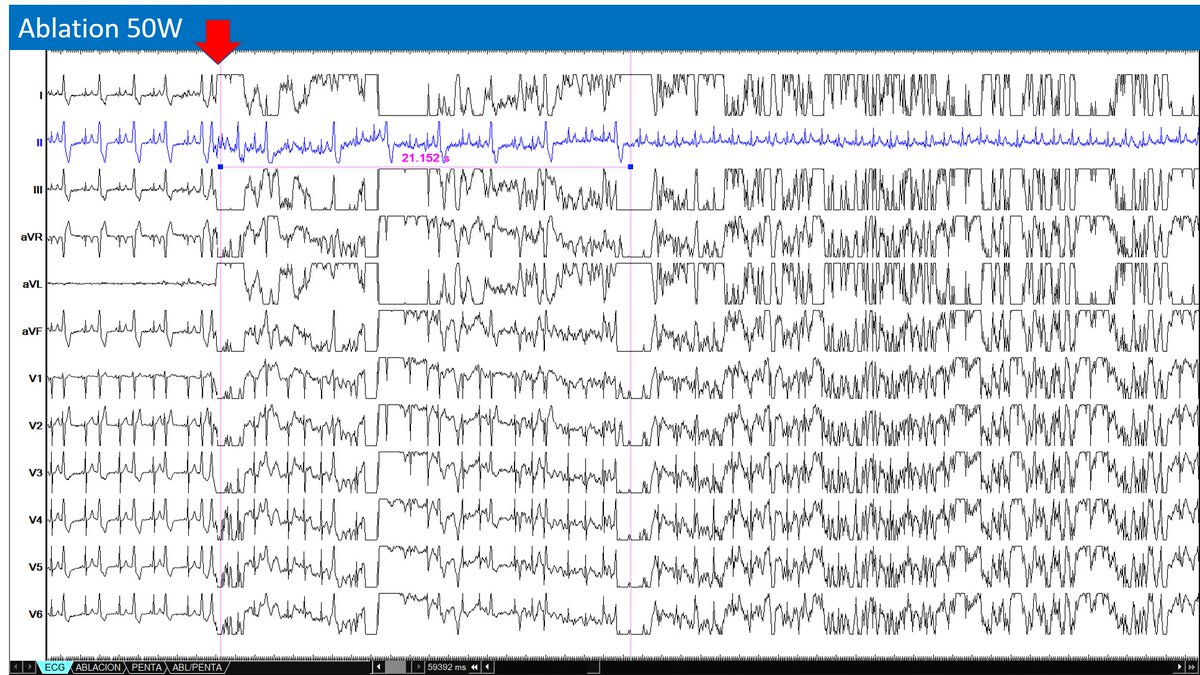

Last surprise of 2022!! 48 year old patient with incessant VT unfortunately with apical thrombus formation.Lucky epicardial VT ablation…#EPeeps

@DrRoderickTung @DrKatrapati @Peteweissmd @su_wilber @MikeZawanehMD Critical isthmus at 11-12 with local EGM stepping out coinciding with TCL jump by 40msec. Suggests circuit has multiple layer components. 12-lead QRS Exit same for both TCL.

Great VT week with @BiosenseWebster! #ablateVT Inferoapical isthmus from large Cx infarction. White line is LOB in ILAM, serving as a surface barrier that forces intramural conduction. Need greater resolve of SNO zone, as it is most critical region. Great collaboration ahead!